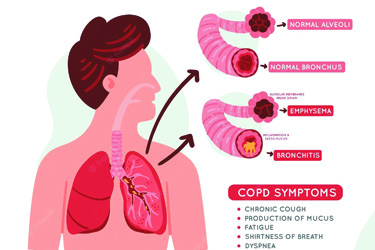

Our Expertise

Critical Care Treatment